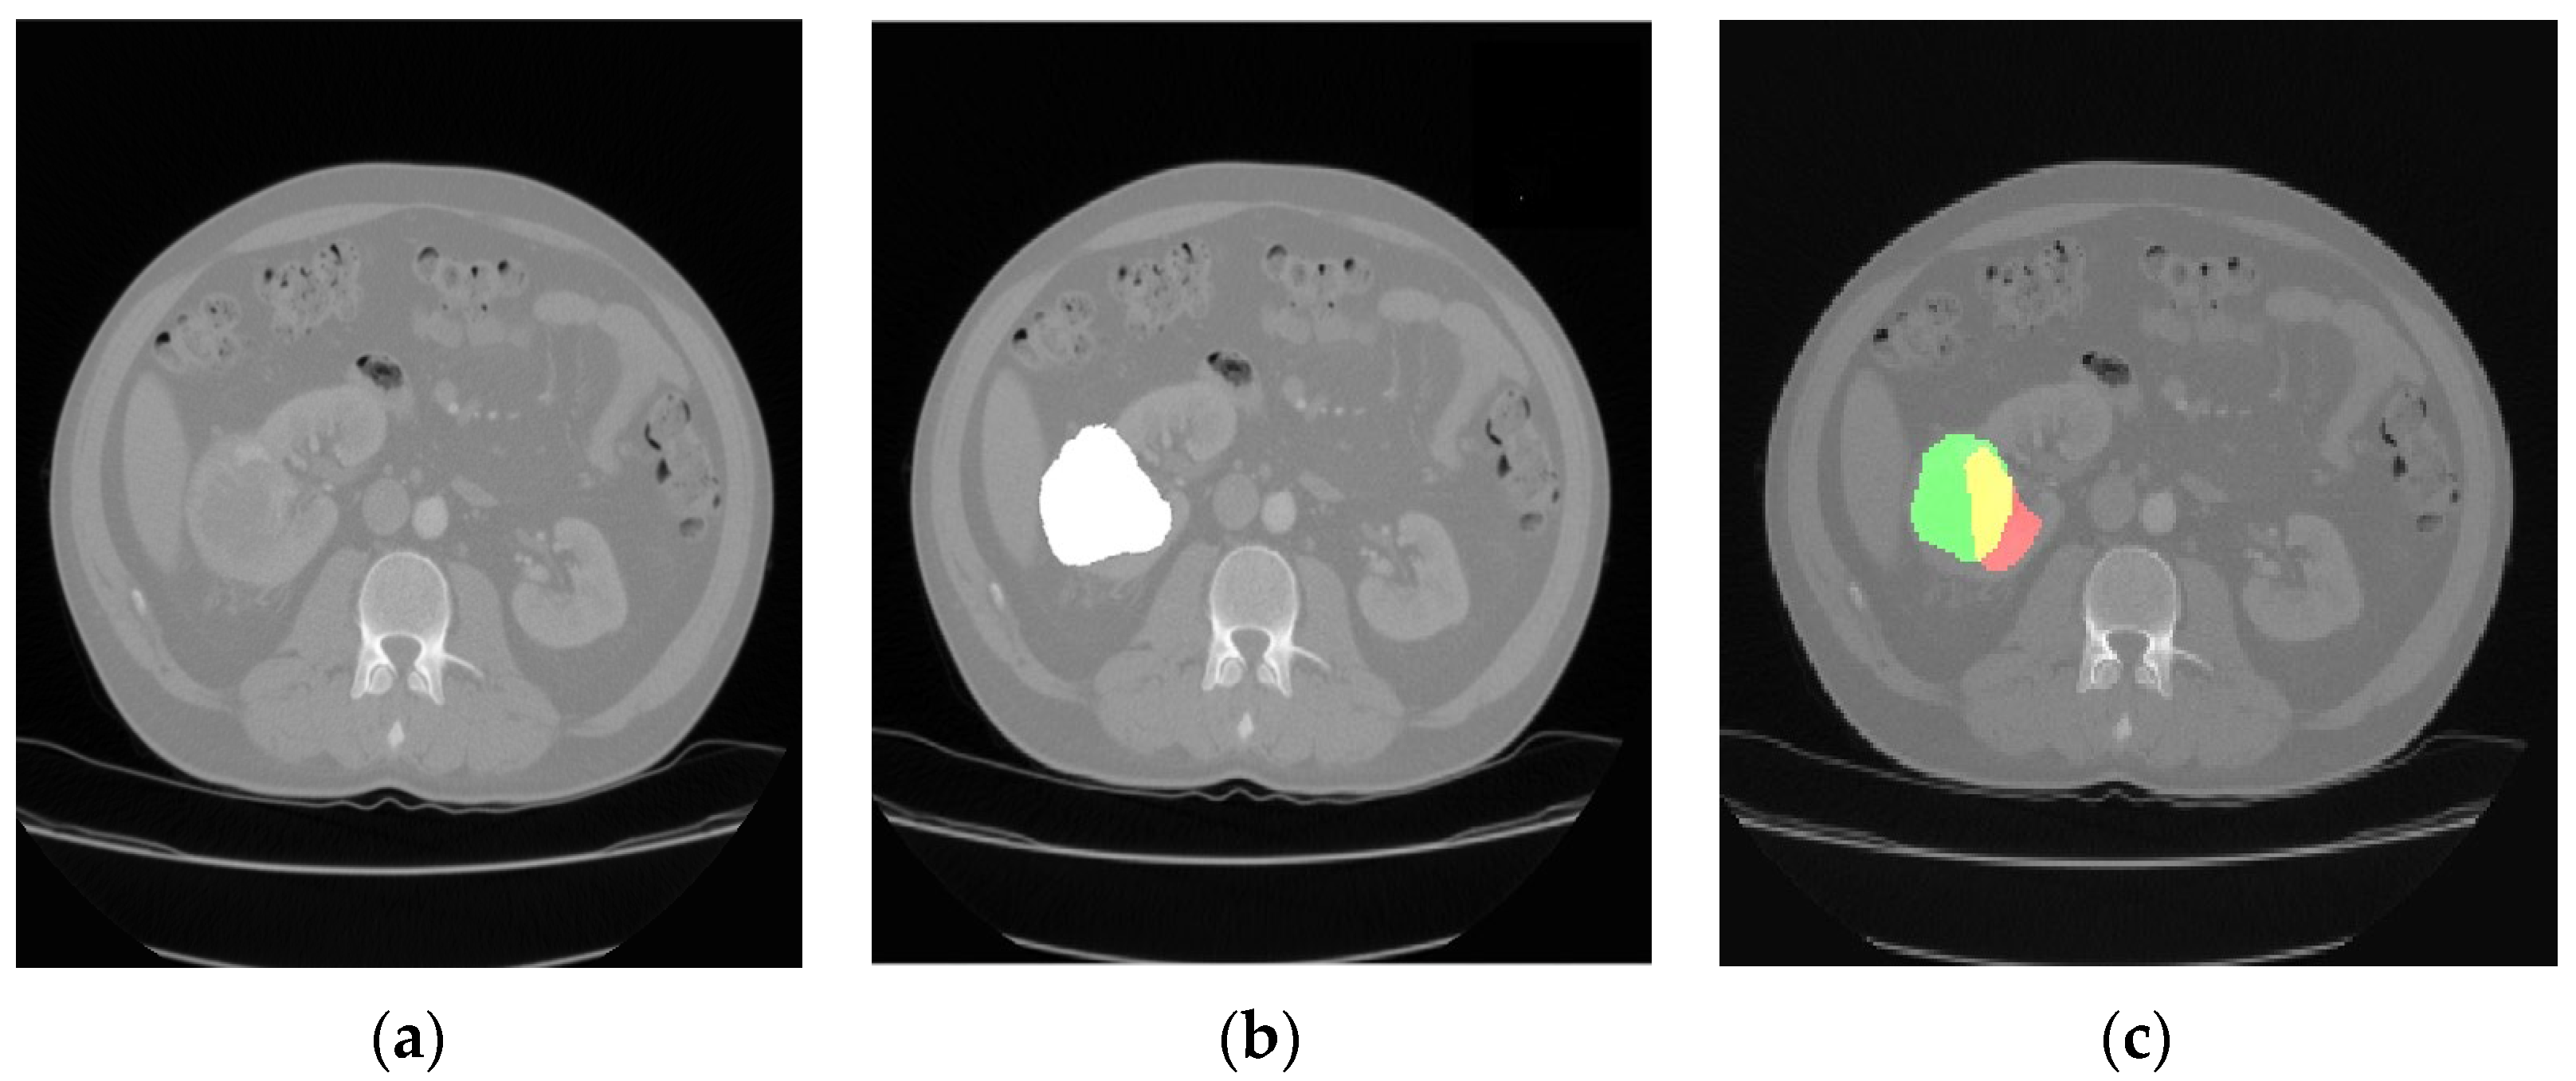

The comparison of the output results of the segmentation network and the expert segmentation of a healthy kidney is shown in Figure 3, while for the pathological kidney (renal tumor), the comparison of the output results of the segmentation network and the expert segmentation of a healthy kidney is shown in Figure 4. Regarding the potential bias of the medical experts, although it cannot be eliminated, we have striven to greatly reduce this bias by triple checking the segmentation of the area of interest. Therefore, a radiology resident (V.O.B.), a radiology fellow (G.M.C.), and a radiology attending physician (C.M.), with a combined 25 years of experience imaging renal cell carcinoma, utilized 3D Slicer [29] to manually segment the dataset. Concerning the color scheme utilized below, the red area represents the prediction, the green area the ground truth. The yellow area, therefore, represents the correctly predicted pixels.

Figure 4. CT image of a kidney with clear cell renal cell carcinoma (a); the medical expert tumor segmentation (shown in white) (b); and the result of the tumor location prediction (c).